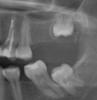

юля. Опубликовано 21 января, 2013 Поделиться Опубликовано 21 января, 2013 добрый вечер хочу поставить имплант можно ли обойтись без наращивания кости Ссылка на комментарий

IvanK Опубликовано 21 января, 2013 Поделиться Опубликовано 21 января, 2013 Для начала рекомендовал бы сходить на консультацию к ортодонту. Синус-лифтинг скорее всего понадобится. + удаление 8-ок. Планировал бы по ДКТ (3Д-снимок)А есть снимок целиком? Ссылка на комментарий

Bier Опубликовано 21 января, 2013 Поделиться Опубликовано 21 января, 2013 Синуслифт тут не нужен, имплантат наверх поставить можно, нужно удалить все 8ки, выровнять и внедрить 7ки внизу имплантировать 6 ые зубы на н.ч. Ссылка на комментарий

IvanK Опубликовано 21 января, 2013 Поделиться Опубликовано 21 января, 2013 Повторюсь, я бы планировал по ДКТ.В остальном согласен с... имплантат наверх поставить можно, нужно удалить все 8ки, выровнять и внедрить 7ки внизу имплантировать 6 ые зубы на н.ч. Ссылка на комментарий